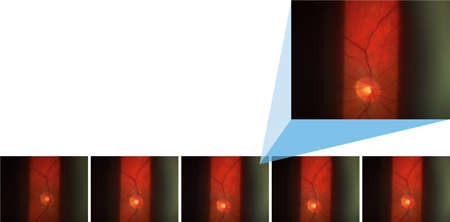

Le système universel de documentation d’images de lampe à fente OCULUS ImageCam®3 n’est pas seulement intuitif et facile à utiliser, il établit également des normes élevées en matière de photographie numérique de lampe à fente. Il s’agit notamment d’un excellent champ de vision qui permet d’établir des diagnostics extrêmement précis des parties antérieure, centrale et postérieure de l’œil. Les images sont capturées par une caméra IDS particulièrement performante en basse lumière de la famille USB3 uEye+ CP.

« Seule une caméra sensible fournit des images à faible bruit dans les situations de prise de vue difficiles au niveau de l’œil », explique Michael Moos, chef de produit chez OCULUS, à propos du choix du modèle de caméra Un autre critère d’exigence important est la vitesse. « Grâce aux caractéristiques avancées de la caméra, il est possible de prendre des photos en rafale jusqu’à 60 images par seconde. Entre autres, ces prises de vue en série permettent d’enregistrer l’œil dans ses pauses de mouvement. La fonction innovante Frame-Out-Of-Video permet de documenter facilement l’ensemble du processus d’examen à la lampe à fente, les images individuelles de meilleure qualité pouvant ensuite être sélectionnées pour l’analyse », explique Michael Moos. L’OCULUS ImageCam® 3 permet cela sans perte de qualité et en un minimum de temps.

Les photos à la lampe à fente de l’OCULUS ImageCam® 3 permettent de documenter objectivement l’état des yeux afin d’établir un suivi de l’évolution des maladies et de comparer les traitements. Les patients bénéficient également du système de documentation par l’image. Les références visuelles du diagnostic ainsi créées les aident à mieux comprendre leur état et le plan de traitement des médecins. Les résultats obtenus peuvent être enregistrés et archivés en conséquence.